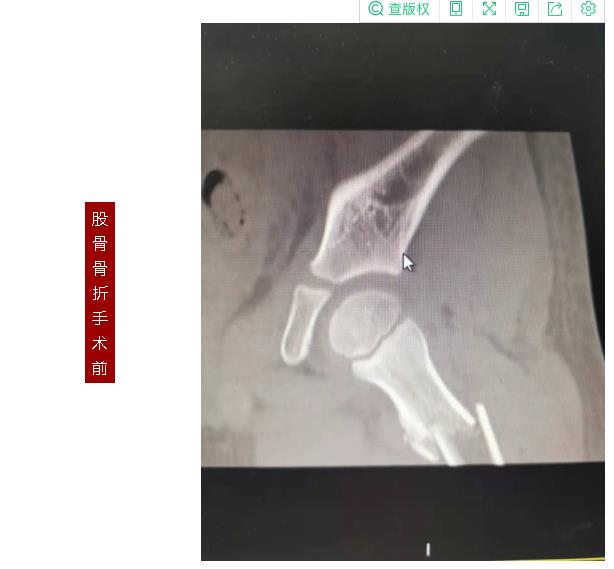

887700线路检测网骨伤二科副主任张永青仔细查看孩子患处,安排其进行放射拍片检查,结果为左侧桡骨颈骨折,根据孩子的骨折状况,张主任认为保守治疗很难做到理想复位,且复位后较难维持良好位置,可能会影响将来前臂的旋转功能,建议孩子尽快接受手术治疗,孩子的家长担心传统手术切口大,孩子所受痛苦多,犹豫不决,张主任与家长沟通,孩子要接受的不是传统的开放手术,而是“骨折闭合复位弹性髓内钉内固定”微创手术,手术只需要一个0.5-1厘米左右的切口就可以达到满意的效果,家长立即同意接受手术治疗。手术非常成功,术后第三天,周周出院。

张永青介绍,“弹性髓内钉技术”是儿童骨科界的一次革命,被誉为上帝赐予长骨骨折儿童的礼物,该项技术可在保护骺板不受损伤的前提下,利用多点固定的原理,微创、有效地治疗4-12岁的四肢骨折患儿,该技术利用钛合金或不锈钢良好的弹性、恢复力将作用于长骨的3个接触点转换成推力和压力,从而使骨折复位,有足够的力量抵抗骨折端移位作用,该方法不需要剥离骨膜和切开骨折端,不干扰骨骺生长,也不破坏骨折端血运,弹性固定、局部微动、创伤小、骨折愈合快,术后3周即可进行功能锻炼,术后1个月功能恢复正常。